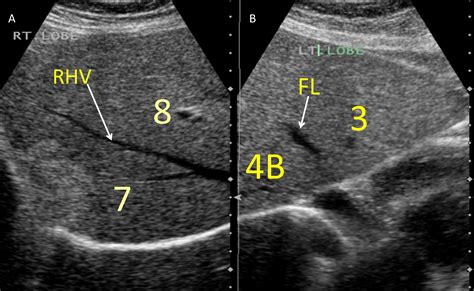

A liver ultrasound is primarily used to screen for abnormalities, monitor chronic liver conditions, or investigate the cause of abdominal pain. When you see pictures of liver ultrasound, you are observing grayscale images generated by sound wave echoes. These echoes bounce off internal tissues and are translated into visual signals by a computer. The liver typically appears as a homogeneous, mid-gray structure, while blood vessels and fluid-filled structures appear darker, and denser tissues like gallstones or scars may appear brighter.

• Fatty Liver Disease: Often characterized by increased brightness (echogenicity) in the liver tissue.

• Cirrhosis: Indicated by a coarse, irregular texture or a shrunken liver surface.

• Liver Masses: Identification of cysts, benign hemangiomas, or malignant tumors.

• Portal Hypertension: Measuring the blood flow through the major veins feeding the liver.